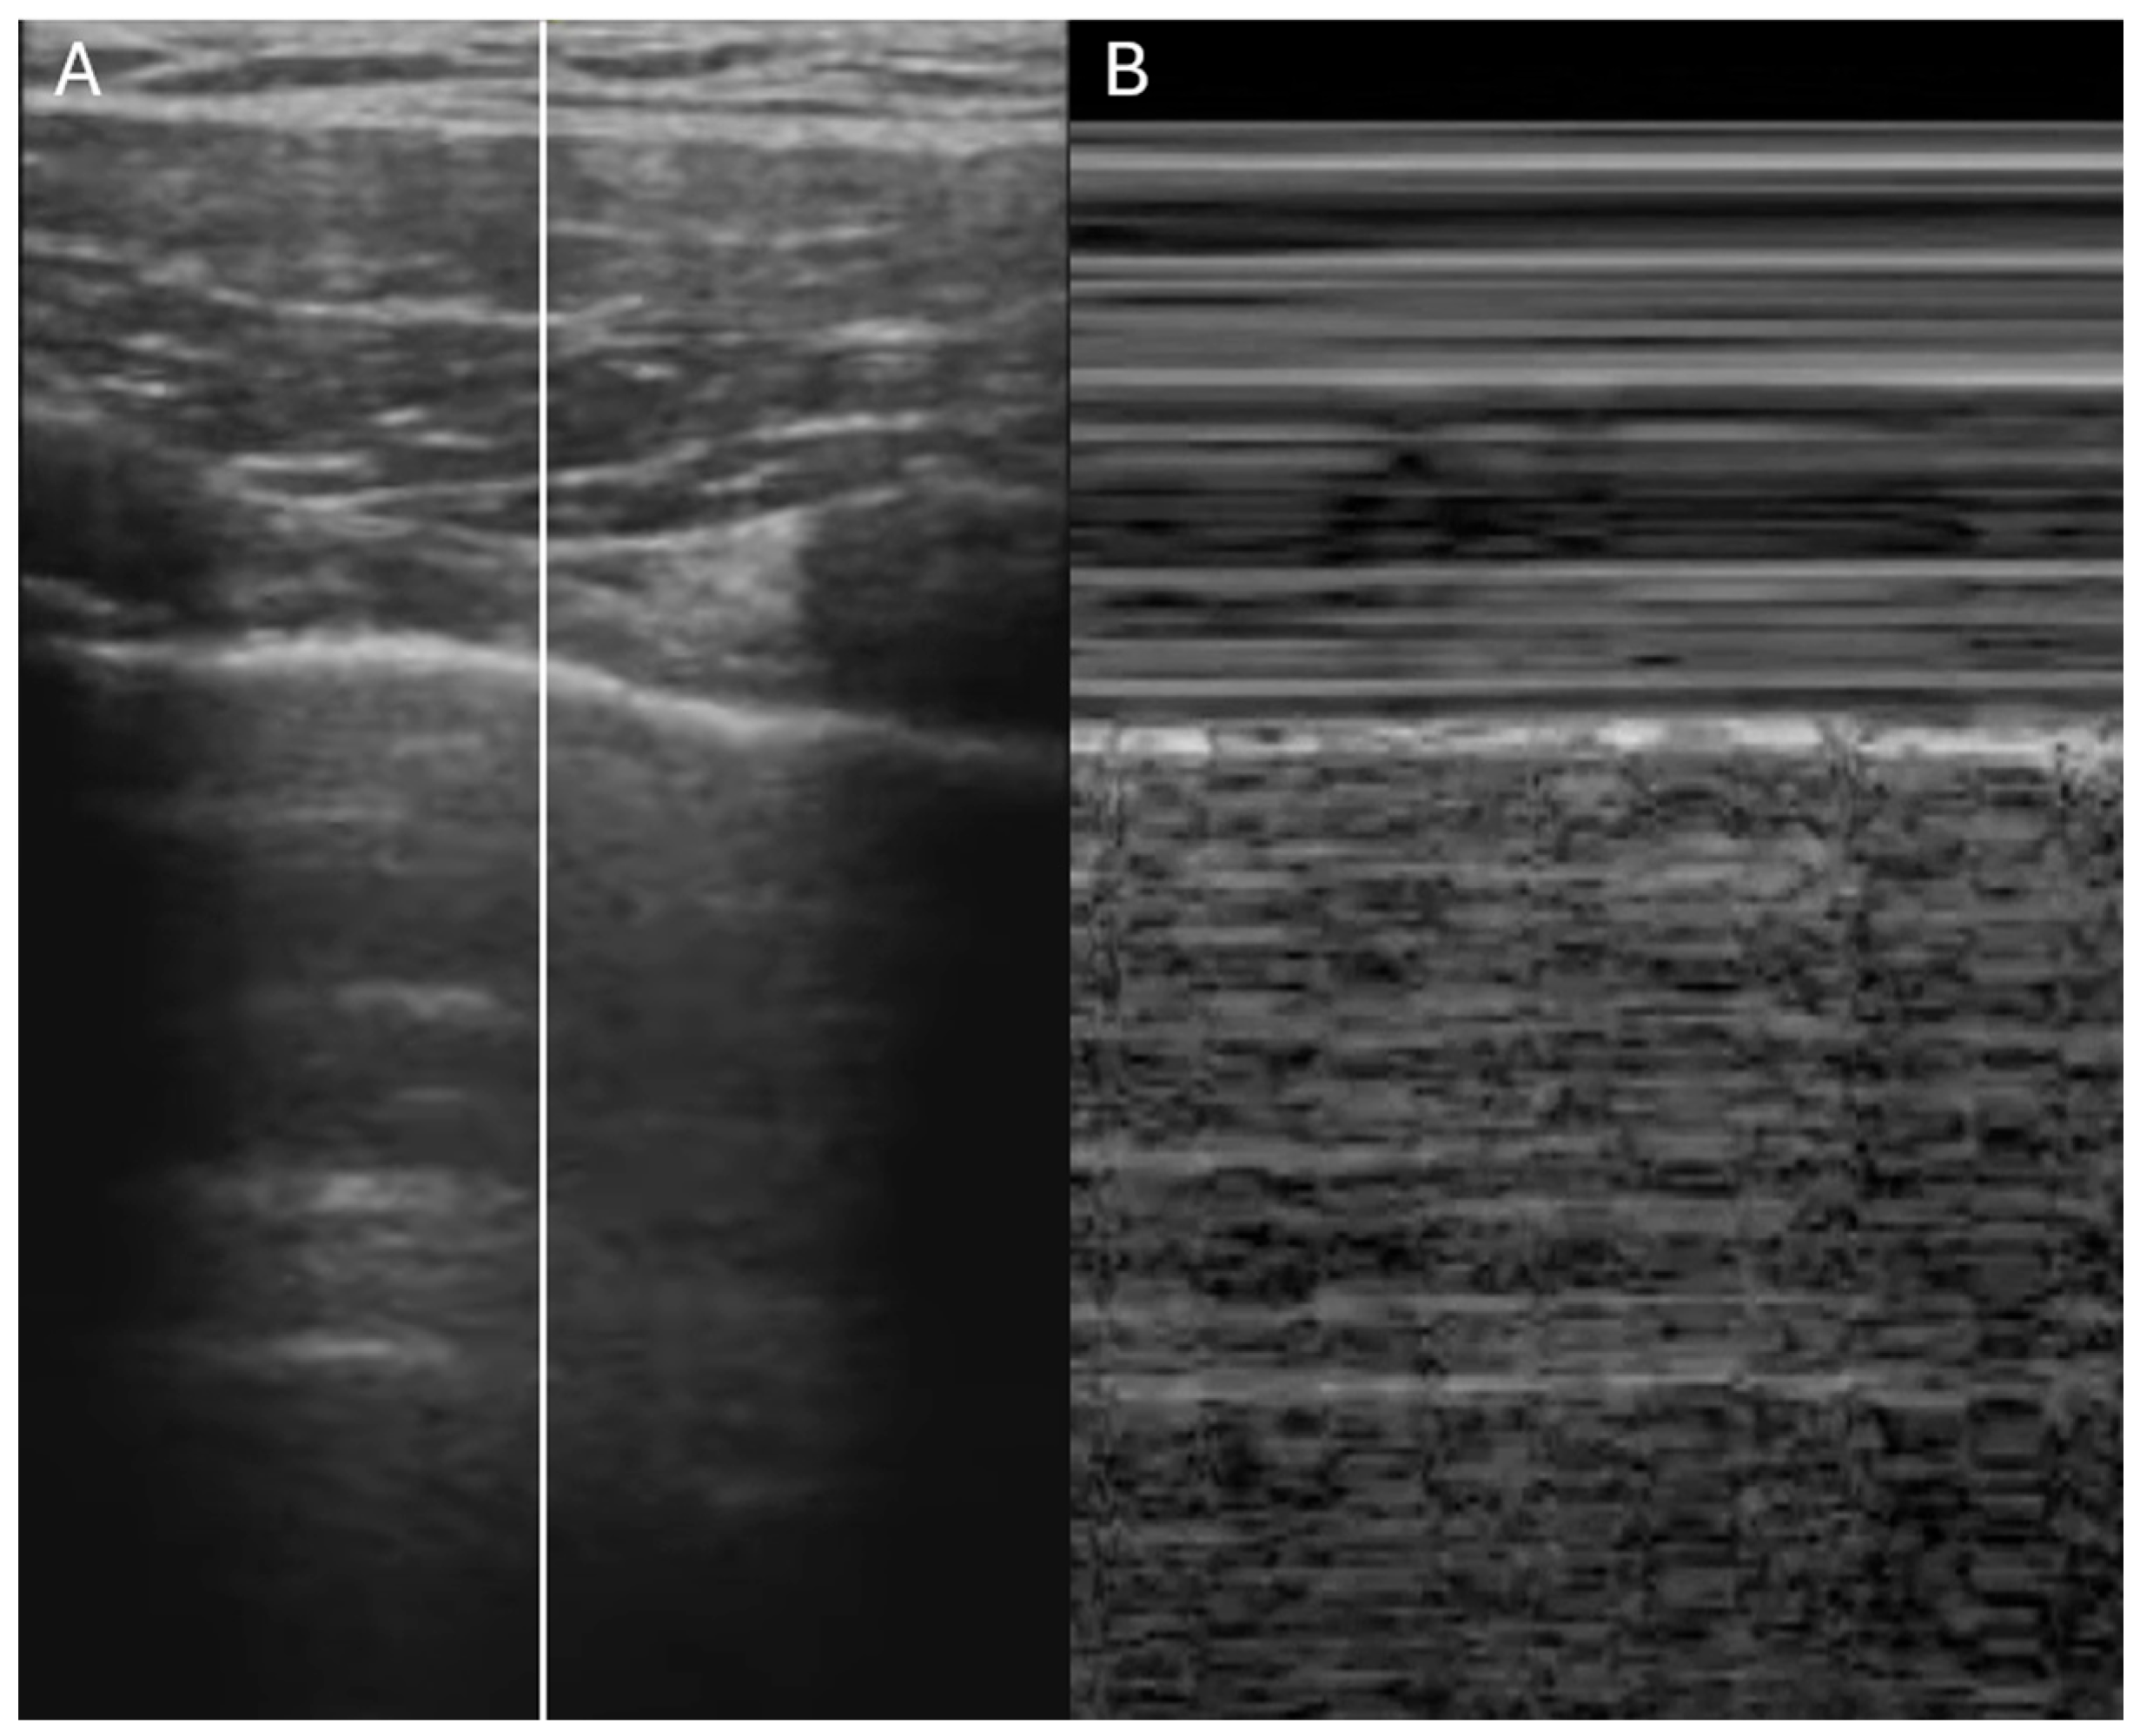

- Ruge, M.; Marhefka, G.D. IVC measurement for the noninvasive evaluation of central venous pressure. J. Echocardiogr. 2022, 20, 133–143. [Google Scholar] [CrossRef]

- Rudski, L.G.; Lai, W.W.; Afilalo, J.; Hua, L.; Handschumacher, M.D.; Chandrasekaran, K.; Solomon, S.D.; Louie, E.K.; Schiller, N.B. Guidelines for the echocardiographic assessment of the right heart in adults: A report from the American Society of Echocardiography endorsed by the European Association of Echocardiography, a registered branch of the European Society of Cardiology, and the Canadian Society of Echocardiography. J. Am. Soc. Echocardiogr. 2010, 23, 685–713. [Google Scholar]

| IVC Diameter | Collapse with Sniff | Estimated RA Pressure |

|---|---|---|

| ≤2.1 cm | >50% | 0–5 mmHg |

| ≤2.1 cm | <50% | 5–10 mmHg |

| >2.1 cm | <50% | 10–20 mmHg |

| IVC diameter & collapsibility | Yes | Yes (with trending) | Yes (plus RA pressure estimate) |